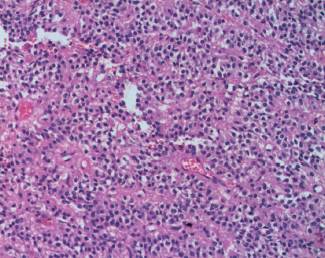

En el procedimiento quirúrgico se logró la resección completa de la tumoración y del polo inferior de bazo por presentar adherencias a cápsula esplénica. Procedimiento sin complicaciones. En el estudio macroscópico la pieza de resección pesó 330 g; al corte era quística con contenido friable, pardo-rojizo oscuro (Figura 2). Las secciones histológicas mostraron amplias áreas de necrosis y hemorragia entre las que se reconocía una proliferación celular atípica que se disponía en patrón pseudopapilar con células poco cohesivas, poligonales, de mediana talla; sus citoplasmas eran claros con ocasionales glóbulos hialinos (Figura 3). Se evidenciaron núcleos con hendiduras y cromatina en grumos, se observaron escasas mitosis típicas. El estroma presentaba áreas hialinizadas, acúmulos de macrófagos espumosos y escasas espículas de colesterol (Figura 4). Las técnicas de inmunohistoquímica mostraron positividad para enolasa, CD56, Fli-1, betacatenina (Figura 5) y vimentina, siendo negativo para sinaptofisina y cromogranina. Basados en estos hallazgos se realizó diagnóstico anatomopatológico de tumor sólido pseudopapilar de páncreas. Los bordes de resección y el parénquima esplénico se encontraban libres de lesión.

Figura 4: Vista a mayor aumento en la que se observa células con citoplasma claro, poco cohesivas en relación a vasos sanguíneos (HE, 400 X).